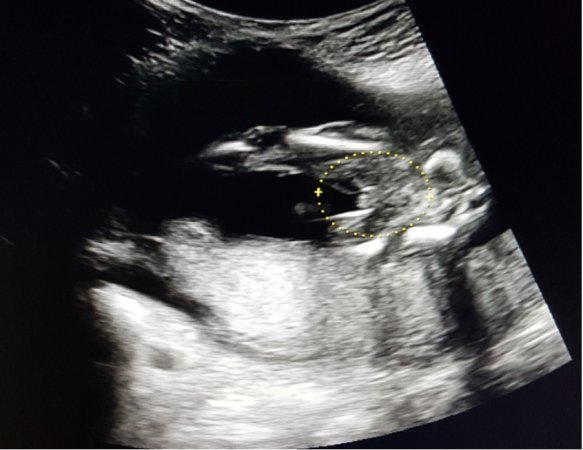

Looks girly. It's kind of an awkward looking potty shot but I don't see anything boyish though.

Is 3 lines always a girl?

3 lines doesn't always mean girl. Sometimes boys can appear to have 3 lines at certain angles. I actually posted about that here several years ago. My DS2 looked like a girl at 16 weeks but he's def a boy!